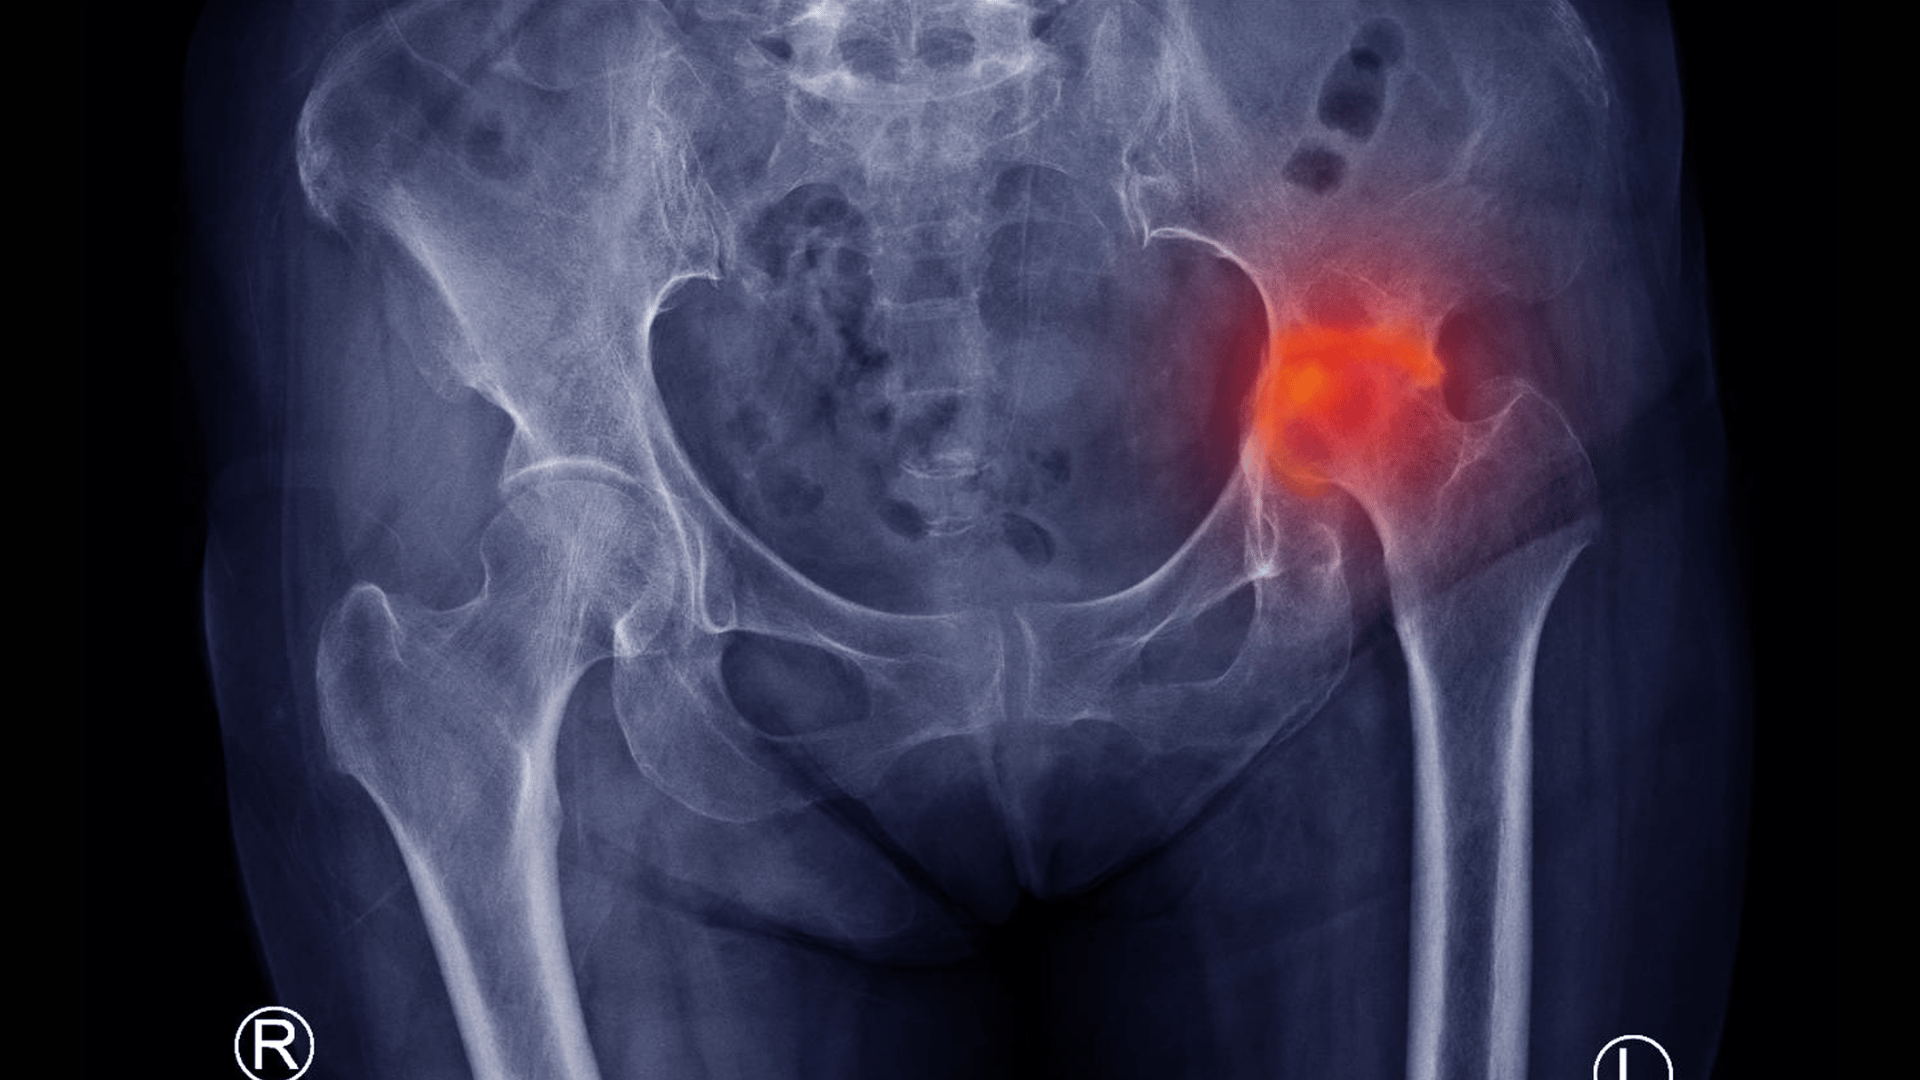

Douleur des hanches

La douleur des hanches est un problème courant qui peut affecter des personnes de tous âges. Elle peut résulter de nombreuses causes, allant de conditions médicales sous-jacentes à des blessures ou des déséquilibres musculaires. Cet article explore en profondeur les différentes causes de la douleur des hanches, les méthodes de diagnostic et les options de...

Coxarthrose

La coxarthrose, également connue sous le nom d’arthrose de la hanche, est une affection courante qui affecte des millions de personnes dans le monde. Cette maladie dégénérative des articulations est caractérisée par la dégradation du cartilage de la hanche, entraînant douleur et limitation des mouvements. Dans cet article, nous explorerons en détail ce qu’est la...

nécrose avasculaire

La nécrose avasculaire (NA), également connue sous le nom d’ostéonécrose, est une condition médicale sérieuse où la mort du tissu osseux survient en raison d’un manque de flux sanguin. Cette affection peut entraîner la destruction de l’os et des articulations environnantes, provoquant des douleurs sévères et une perte de fonction. Cet article explore en profondeur...